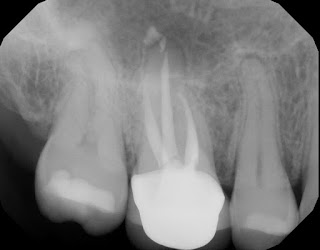

RCT was completed and returned to GP for coronal coverage.

5 year recall of the tooth finds it fully functional and asymptomatic. Note the fine margins of the crown which play a key role in the success of this treatment. Some patients will elect to retain a natural tooth with a crack, understanding the guarded long term prognosis, rather than extract and replace it.